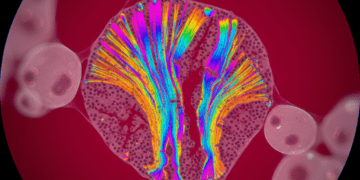

A microscopia confocal é uma técnica de imagem que utiliza lasers para iluminar amostras de forma extremamente específica. A luz laser emite um feixe que penetra na amostra, e um detector captura a luz emitida pela amostra em um ponto focal. Essa abordagem permite a obtenção de cortes ópticos finos, eliminando as distrações de planos fora de foco, que são um desafio comum em técnicas de microscopia tradicionais.

O principal diferencial da microscopia confocal é seu uso do mencionado corte óptico laser. Um feixe de laser é utilizado para iluminar apenas uma parte da amostra em um dado instante. Isso, combinado com um sistema de pinhole que bloqueia a luz indesejada de outros planos, resulta em imagens muito nítidas. Essa técnica é particularmente útil para visualizar estruturas celulares complexas e pode ser aplicada a diversas amostras, incluindo células orais.

O estudo das células orais, como os queratinócitos, fibroblastos e células imunes, é fundamental para compreender várias condições de saúde bucal. Os cortes ópticos gerados pela microscopia confocal permitem que os cientistas investiguem a morfologia, organização e comportamento dessas células de maneira detalhada.

A capacidade de visualizar cortes múltiplos em 3D tem facilitado a identificação precoce de doenças bucais, como lesões neoplásicas e infecções. As imagens 3D celulares extraídas por meio da microscopia confocal proporcionam insights sobre como as células interagem entre si e podem servir como indicadores de progressão de doenças.

Após a captura de cortes ópticos pela microscopia confocal, as imagens podem ser processadas por softwares especializados para criar reconstruções tridimensionais. Este processo envolve a montagem de múltiplas camadas de imagens em um único modelo 3D, permitindo análises mais profundas e detalhadas.

Os softwares de reconstrução são projetados para combinar as imagens obtidas em diferentes planos focais, resultando em um modelo tridimensional. Com essa tecnologia, pesquisadores podem manipular a visualização, rotacionando e ampliando o modelo para examinar detalhes específicos. Isso é essencial para estudos em citologia e pode ser acessado em detalhes em nosso site sobre citologia.